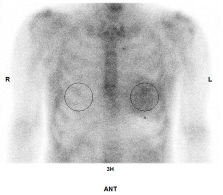

心アミロイドーシスは、心臓にアミロイドと呼ばれる異常なタンパク質が沈着し、形態的かつ/または機能的な異常をきたす疾患群です。診断には、心アミロイドーシスを疑うRed-flag所見、つまり手根管症候群/脊柱管狭窄症の既往、心電図での低電位・前胸部誘導でのR波増工不良、心エコーでの左室肥大を伴う高齢心不全、大動脈弁狭窄症などを理解し、保険収載された骨シンチによる評価とM蛋白の評価を組み合わせることが重要です。特にNYHA心機能分類I/II度のATTR心アミロイドーシス患者に対するTTR四量体安定化薬の投与は推奨クラスIとなっています。

当院での1例を示します。

79才、男性。主訴は労作時息切れ。心臓超音波検査で左室肥大を認め紹介頂きました。採血でNT-pro BNP 2142pg/ml、Troponin T 0.061ng/ml, 心臓超音波検査で左室中隔厚は18.3mm、GLSでapical sparing (図3)を認めました。骨シンチで心臓にGrade 3の集積(図4)を認め、右室中隔からの心筋生検で心アミロイドーシスと診断。現在タファミディス(ビンマック61mg/日)内服中です。